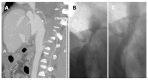

Orthotopic liver transplantation (OLT) represents a major treatment for end-stage chronic liver disease, as well as selected cases of hepatocellular carcinoma and acute liver failure. The ever-increasing development of imaging modalities significantly contributed, over the last decades, to the management of recipients both in the pre-operative and post-operative period, thus impacting on graft and patients survival. When properly used, imaging modalities such as ultrasound, multidetector computed tomography, magnetic resonance imaging (MRI) and procedures of direct cholangiography are capable to provide rapid and reliable recognition and treatment of vascular and biliary complications occurring after OLT. Less defined is the role for imaging in assessing primary graft dysfunction (including rejection) or chronic allograft disease after OLT, e.g., hepatitis C virus (HCV) recurrence. This paper: (1) describes specific characteristic of the above imaging modalities and the rationale for their use in clinical practice; (2) illustrates main imaging findings related to post-OLT complications in adult patients; and (3) reviews future perspectives emerging in the surveillance of recipients with HCV recurrence, with special emphasis on MRI.